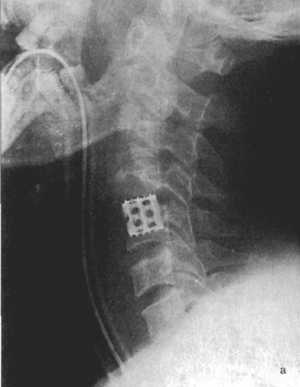

Рис. 3.5: а - травматический вывих С5-С6 позвонков;

б - межтеловая стабилизации металлическим цилиндром сразу после операции;

в - через 3 года после операции. |